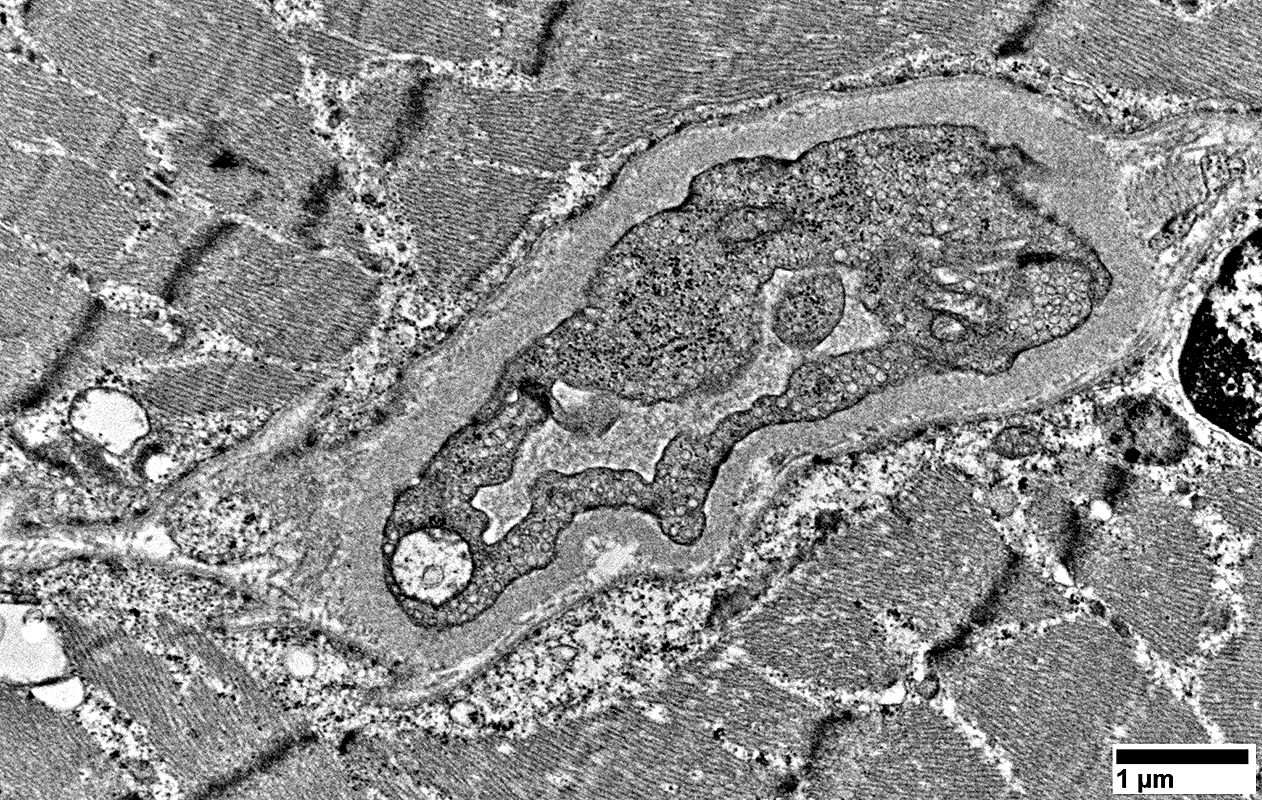

MELAS: Capillaries

From: R Schmidt

Endomysial vessels with

Large endothelial cells with many vesicles

No lumen

Many smooth muscle cells in wall, some with mitochondrial proliferation (Arrow)

Thick wall